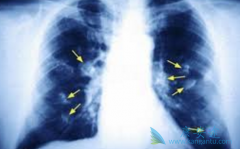

• 晚期肺癌能治吗?治疗方法有哪些?

晚期肺癌能治吗?治疗方法有哪些?

肺癌患者往往发现的时候已经是中晚期了,早期肺癌症状类似感冒咳嗽,很容易被患者忽视,不治疗身体也没出现大的问题,就没在意,当几年后突然检查时,医生告知肺癌晚期。那么, 晚期肺癌能治吗 ?当然是可以的,肺癌晚期可以选择外科的治疗,比如放射性 ...

• 肺癌能治好吗?肺癌中晚期治疗方案有哪些?

肺癌能治好吗?肺癌中晚期治疗方案有哪些?

现在大家都谈癌色变,一旦得了癌症就觉得离死不远了。其实,随着检查手段和医疗技术的发展,很多癌症现在都是可以治愈的,就算是一些不能治愈的癌症,也可以通过一系列的治疗实现带瘤生存。以肺癌为例,如果患者能够在早期发现病情,一般手术加上一些辅 ...